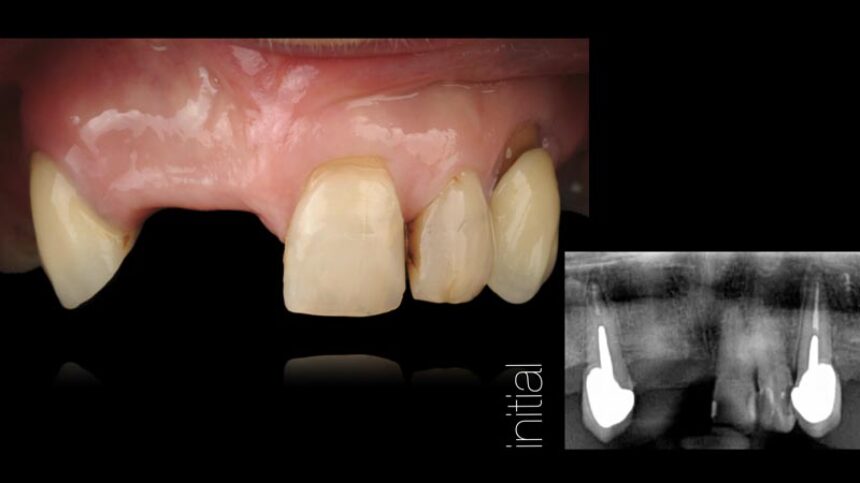

Aesthetic Implant Dentistry – basic science

Anatomical determinants of aesthetic implant restoration – Diagnosis and treatment planning.

Soft Tissue management.

Surgical techniques for hard and soft tissue augmentation.